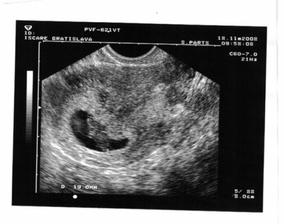

18.11.2008 - sme 9tt+2, krpček má 19 mm